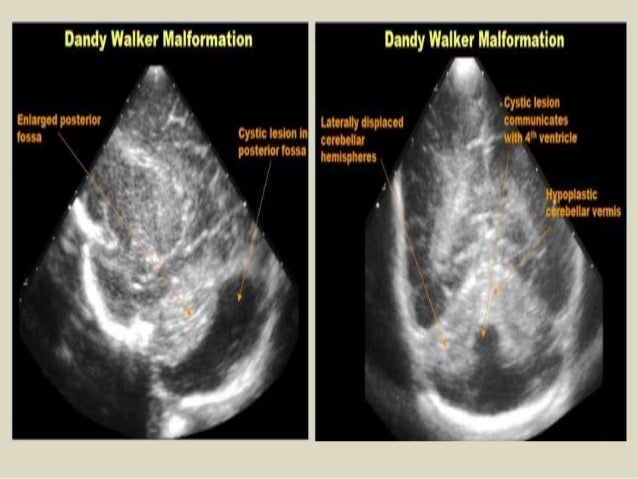

30. 30. Coronal section - Dandy - Walker malformation - dilation of the fourth ventricle (blue star), hypoplastic cerebellar hemispheres.